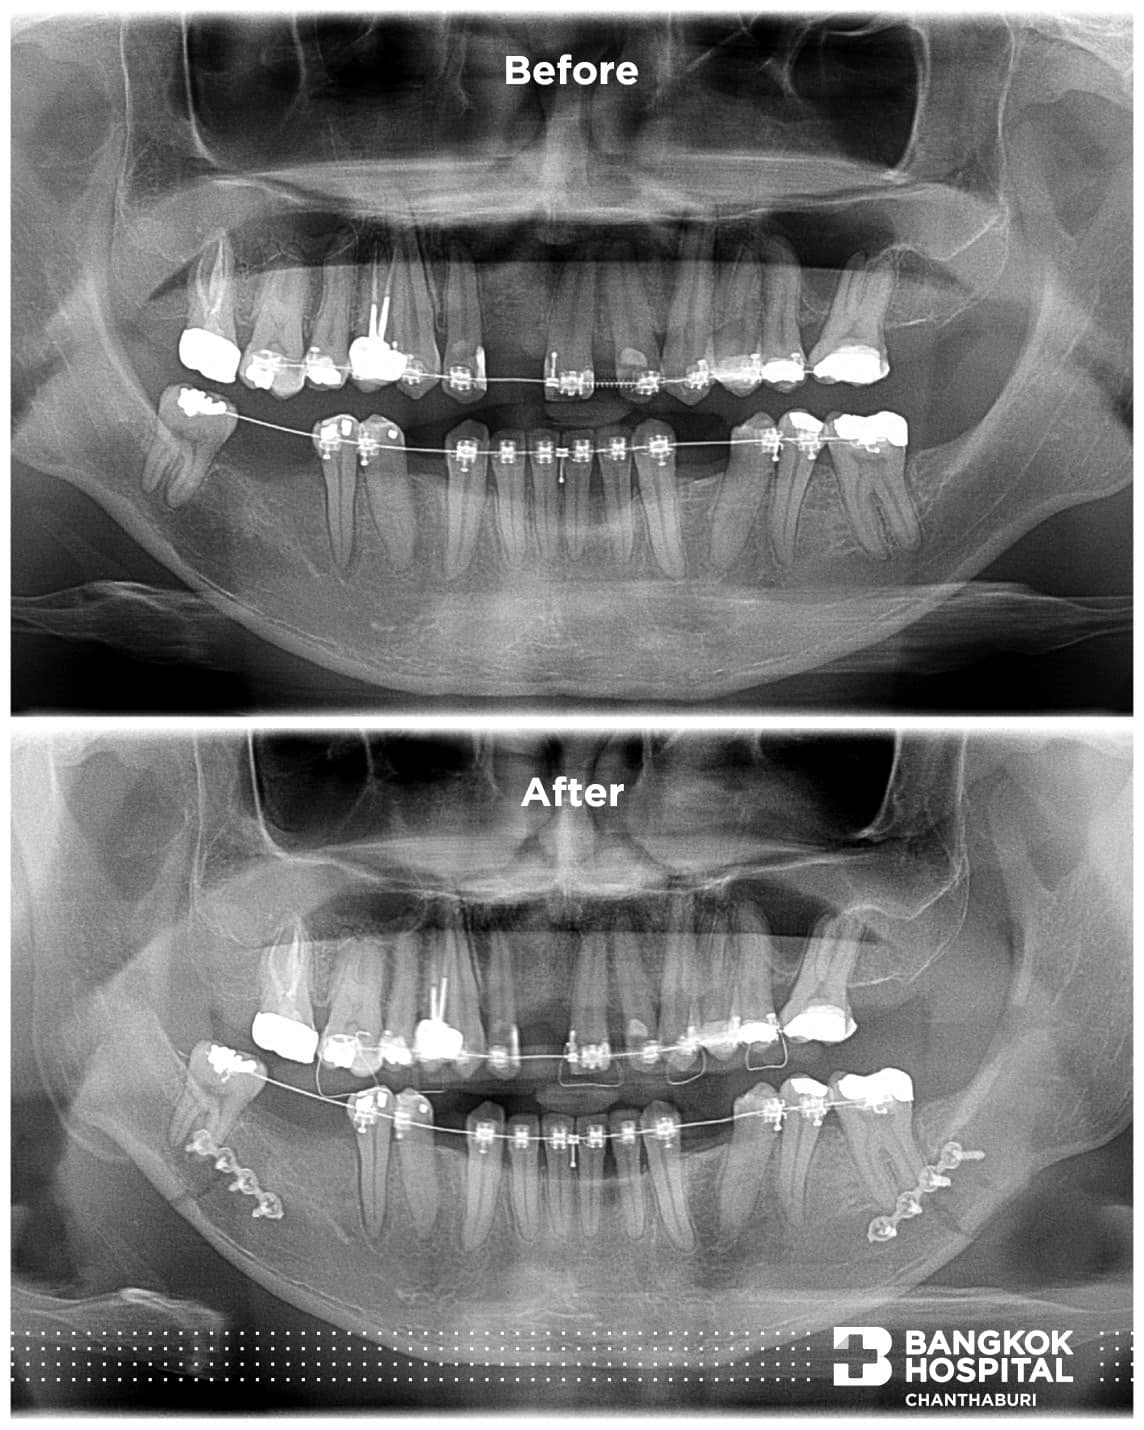

BSSRO (Bilateral Sagittal Split Ramus Osteotomy) การผ่าตัดขากรรไกรล่างที่ช่วยปรับสมดุลของขากรรไกรและฟันได้อย่างมีประสิทธิภาพ พร้อมเปลี่ยนแปลงชีวิตคุณในทุกมิติ

– แก้ไขความผิดปกติขากรรไกรล่าง ที่ภาวะกระดูกขากรรไกรล่างยื่น ถอย และเบี้ยว

– แก้ไขความผิดปกติในการสบฟัน หรือตำแหน่งที่ฟันไม่สัมผัสกันเมื่อกัดฟันเต็มที่

– แก้ไขรูปหน้าที่ไม่สมมาตร หรือผิดสัดส่วนเช่น คางสั้น ยิ้มเห็นเหงือกมาก คางยื่น หรือปากอูมผิดปกติ